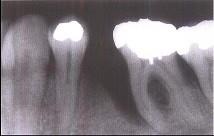

牙槽骨垂直型吸收的特点,除外 ( )

- A.牙槽骨不发生水平方向的吸收

- B.牙槽嵴高度降低不多,而牙根周围的骨吸收较多

- C.垂直吸收多形成骨下袋

- D.牙槽骨发生垂直或斜型方向的吸收

- E.与牙根面形成角型的骨缺损

A